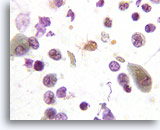

Figure 169

Hyperplasia

Reserve cell hyperplasia is characterized by tight clusters of small reserve cells.

Hyperplasia

Reserve cell hyperplasia is characterized by tight clusters of small reserve cells.

Figure 169

Hyperplasia

Reserve cell hyperplasia is characterized by tight clusters of small reserve cells.

Hyperplasia

Reserve cell hyperplasia is characterized by tight clusters of small reserve cells.